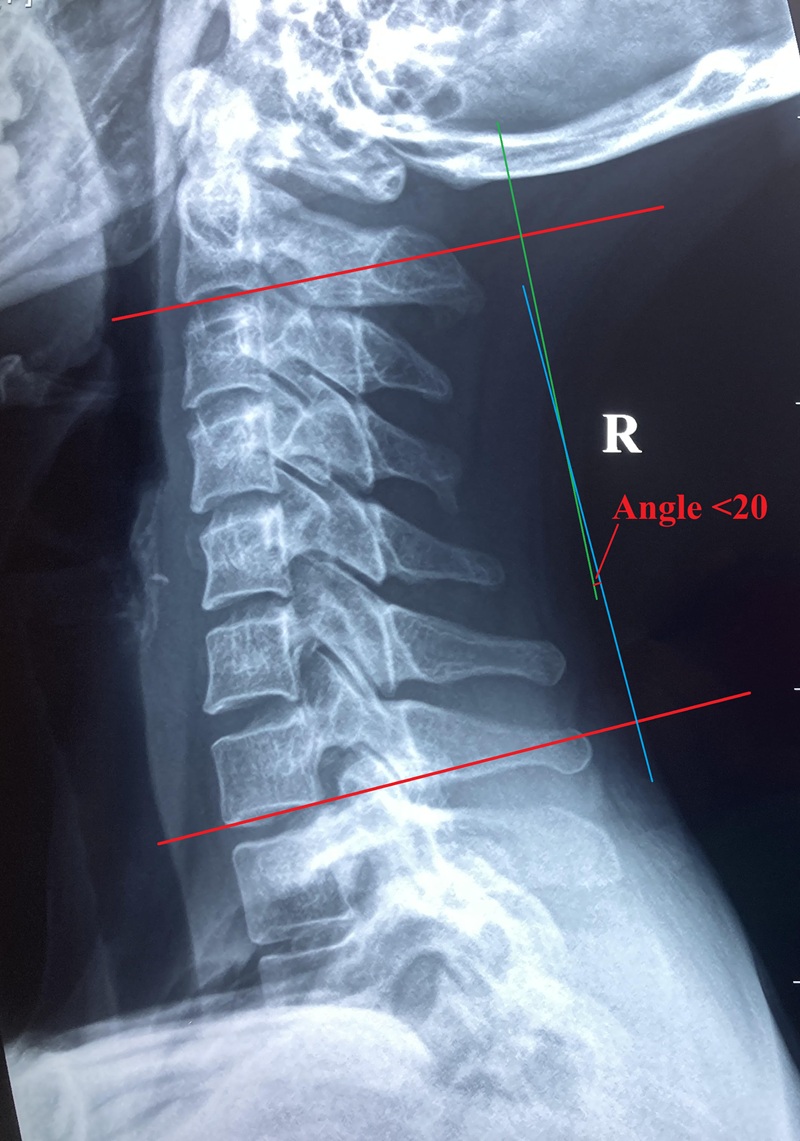

Neck is formed by seven cervical vertebrae, it supports the skull which is approximately about 6-8% of total body weight. Neck is strong but it is also flexible enough for allowing a wide range of motion. The joints in the neck allow six degrees of motions, namely, bending forward, extending backward, bending sideways and turning. Unique and functional sharps of each neck bone allowing fulfilment of different directions of movement. For instance, the first neck bone Atlas looks like a ring sitting on a protrusion sharp structure of the second cervical bone, allowing a wild angle of turning range of motion in the neck area. While the remaining lower neck bones allow mainly side bending motions.